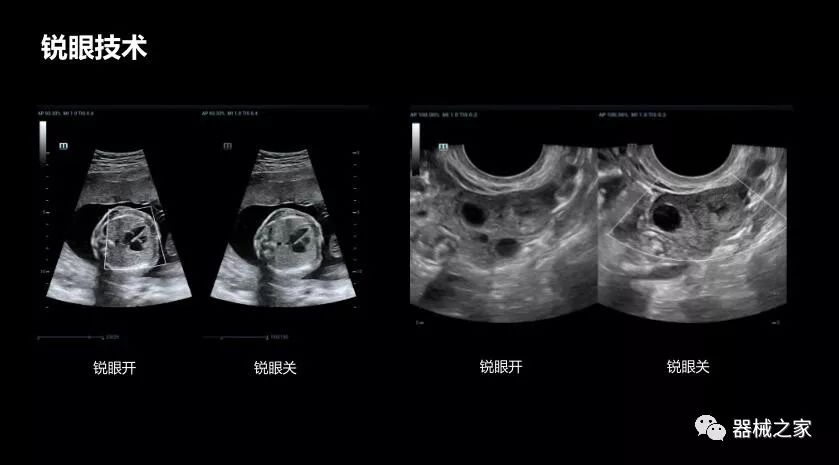

銳眼技術(shù)

做胎兒心臟檢查的時候,如果是聲窗不好的孕婦,很難看清胎兒心腔 。女媧Resona 8的銳眼技術(shù)能很好的優(yōu)化心腔內(nèi)的噪聲,讓胎心結(jié)構(gòu)完美的呈現(xiàn)。